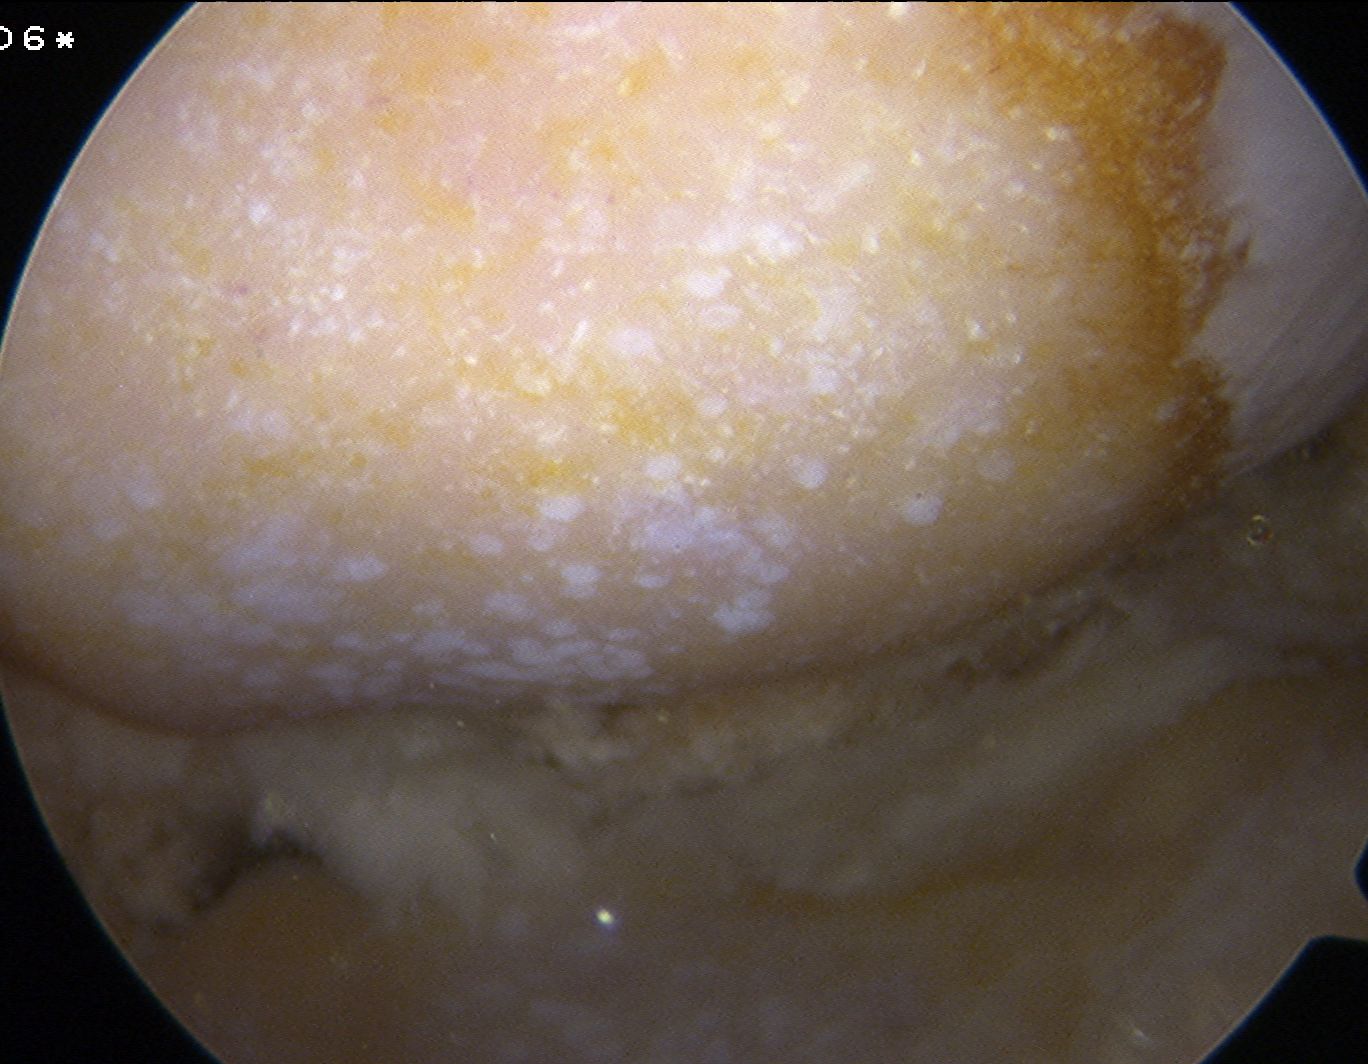

Chronic chondrocalcinosis predisposes to development of 2° OA

- crystals embedded in articular cartilage have desiccating effect

3. Chronic CPPD Arthropathy

OA 2° CPPD

Pseudo-Osteoarthritis

- polyarticular disease like OA

- in hips & knees

- due to CPPD in cartilage altering the biomechanics